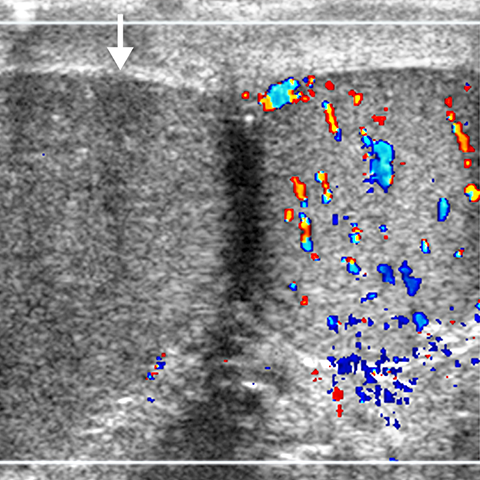

Acute Testicular Torsion [2 of 3]